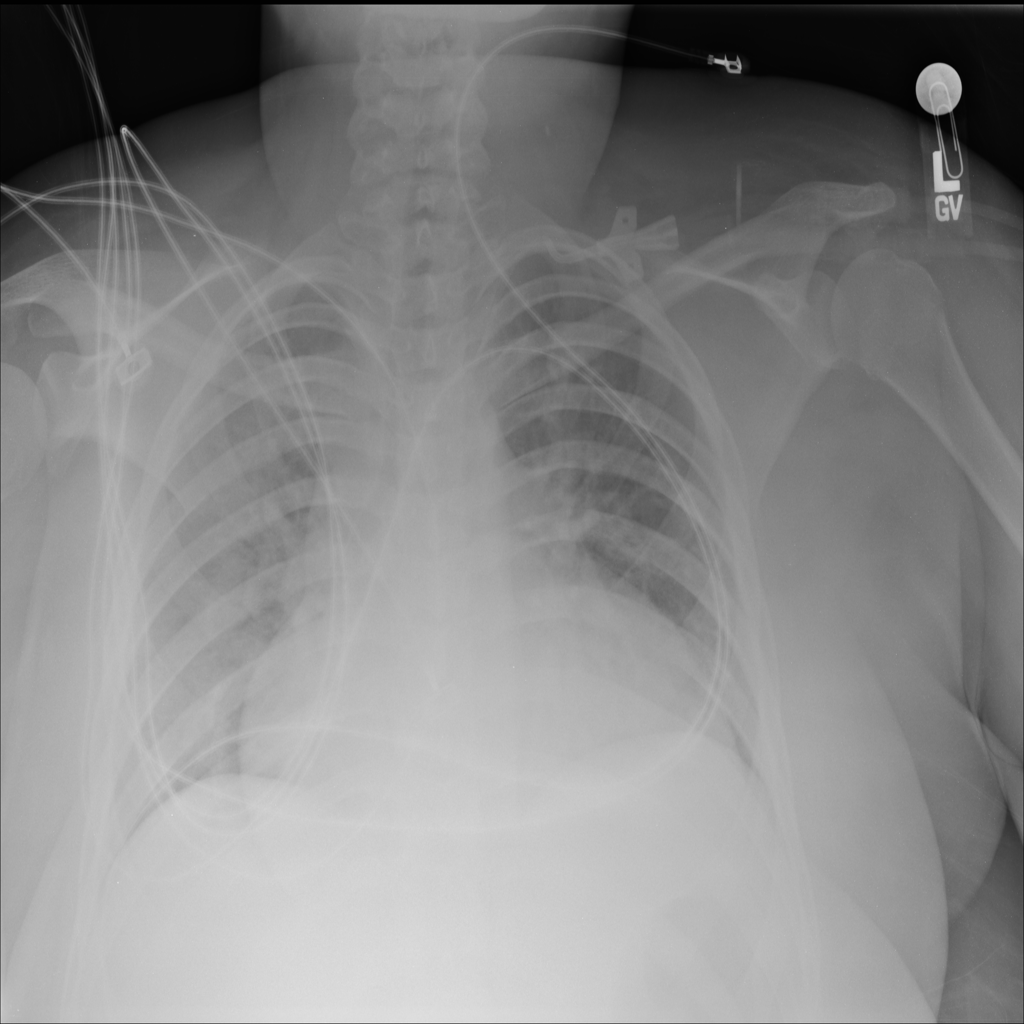

PAT-24D9 · IMG-006Edema

PAT-24D9 · IMG-006

AP